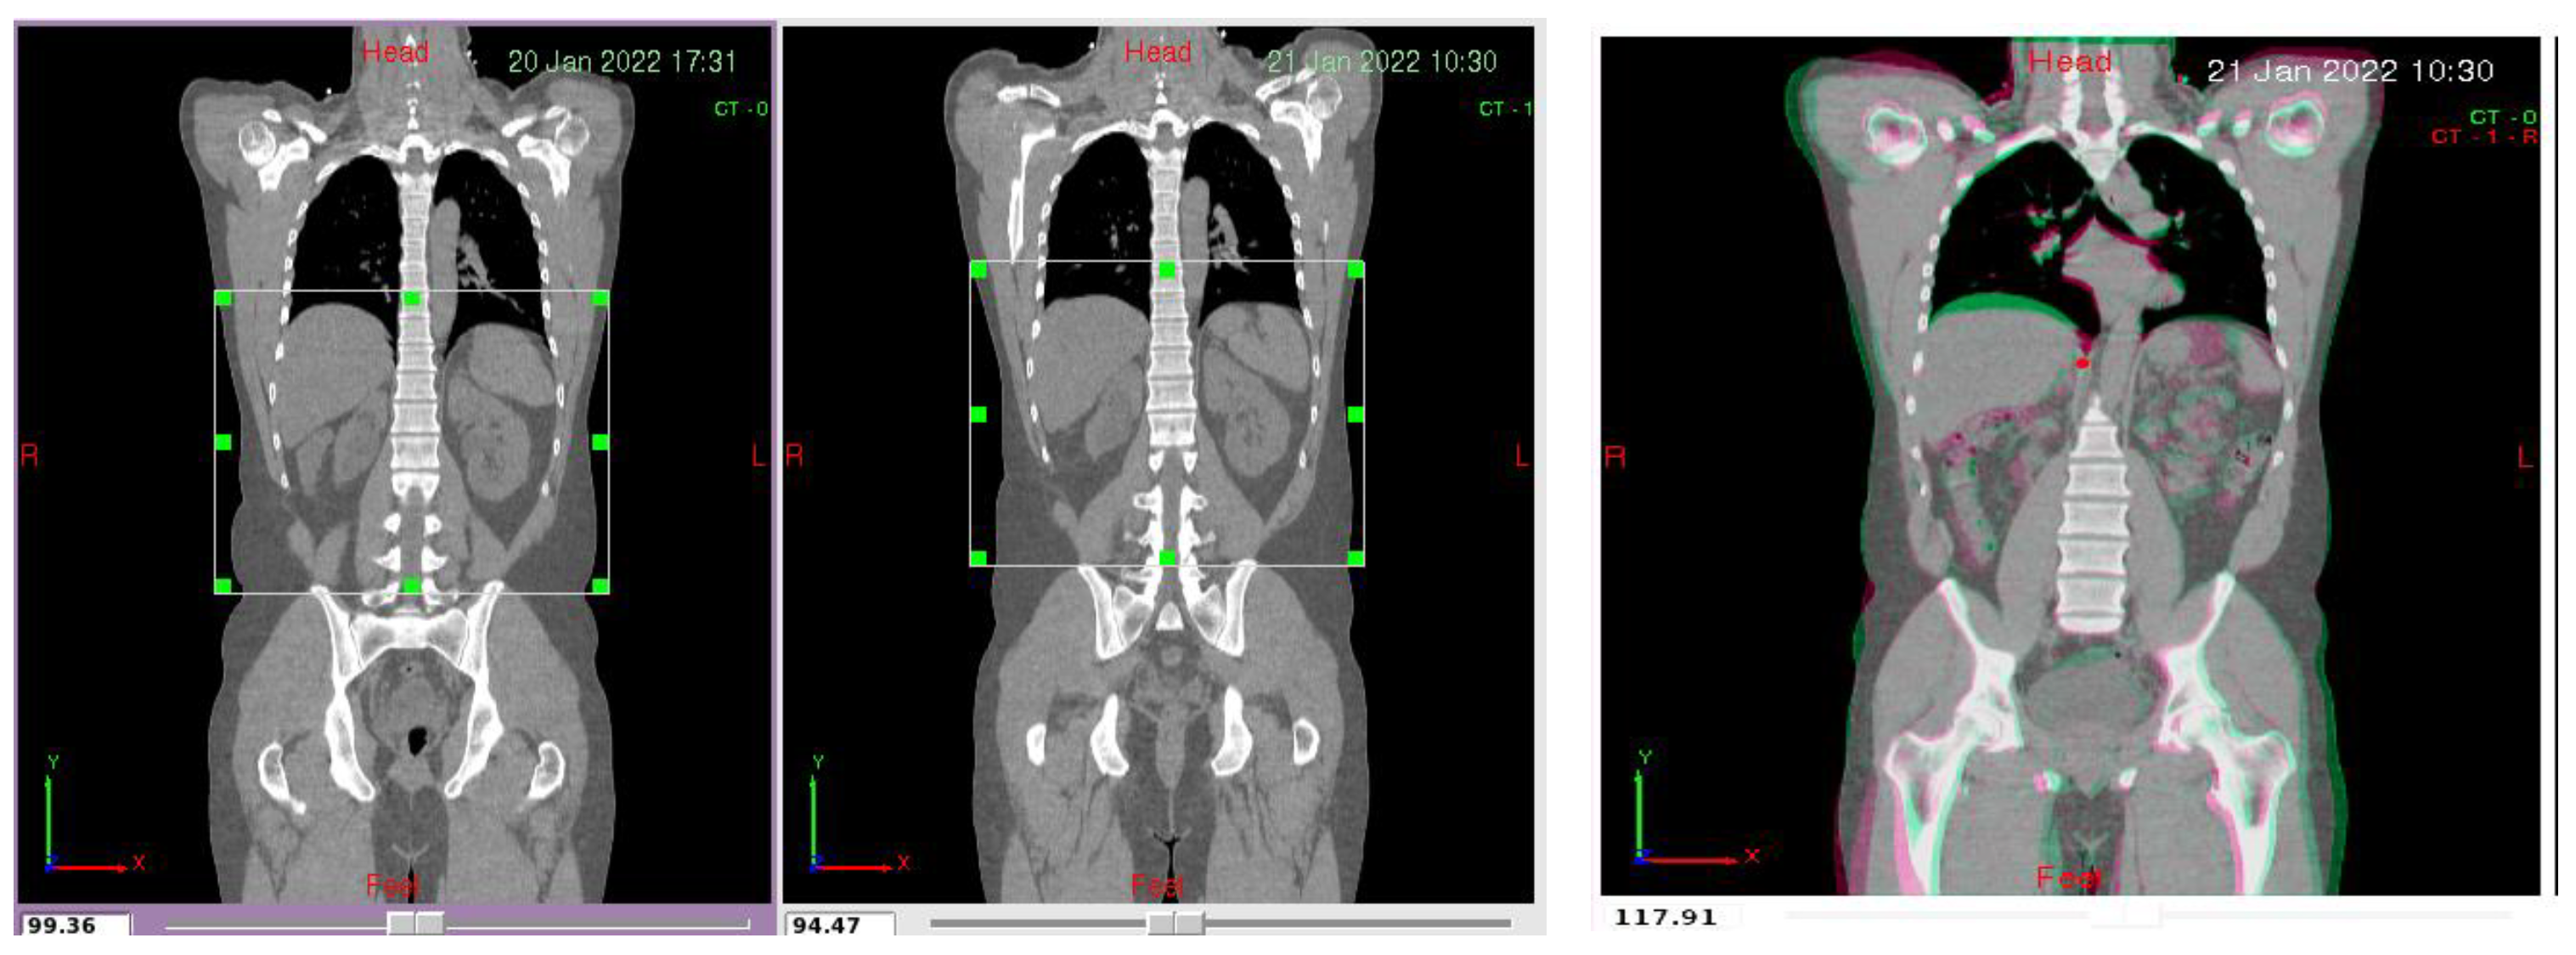

2.4. Pre-Processing